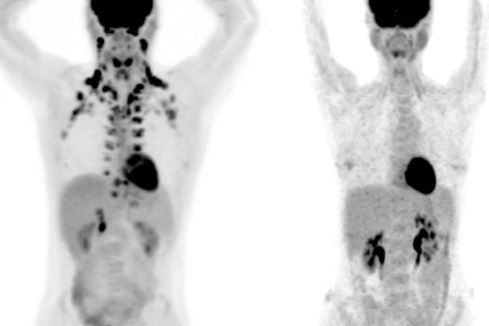

Σε αυτές τις εξετάσεις PET, το άτομο στα αριστερά έχει άφθονο καφέ λίπος γύρω από τον λαιμό και την αυχενική μοίρα της σπονδυλικής στήλης. Το άτομο στα δεξιά δεν έχει ανιχνεύσιμο καφέ λίπος.

Οι μελέτες μεγάλης κλίμακας για το καφέ λίπος, ωστόσο, ήταν πρακτικά αδύνατες, επειδή αυτός ο ιστός εμφανίζεται μόνο σε εξετάσεις PET, έναν ειδικό τύπο ιατρικής απεικόνισης. «Αυτές οι εξετάσεις είναι ακριβές, αλλά το σημαντικότερο είναι ότι χρησιμοποιούν ακτινοβολία», λέει ο Tobias Becher, πρώτος συγγραφέας της μελέτης και πρώην Clinical Scholar στο εργαστήριο του Cohen. «Δεν θέλουμε να υποβάλλουμε πολλούς υγιείς ανθρώπους σε κάτι τέτοιο».